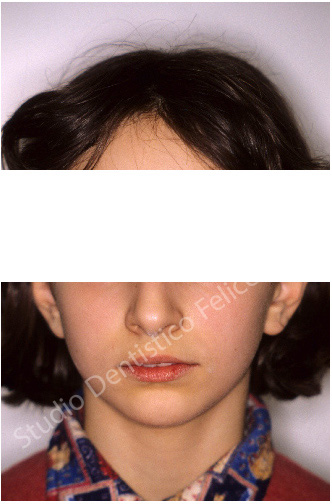

IL CASO DI ALESSANDRA (ORTODONZIA MOBILE IIA CLASSE)

IIa classe da Iposviluppo dello scheletro inferiore o mandibolare trattata, in fase di crescita con apparecchio rimovibile. Apparentemente una sporgenza dei denti incisivi superiori, in realtà un arretramento notevole del mento (parte inferiore). Anche qui un intervento precoce in età prepuberale ha permesso di stimolare la crescita della parte inferiore che venendo in avanti ha migliorato il viso. Guardando le foto di profilo prima e dopo si può notare il miglioramento estetico per avanzamento mandibolare (mento).Sorriso perfetto e viso in armonia.